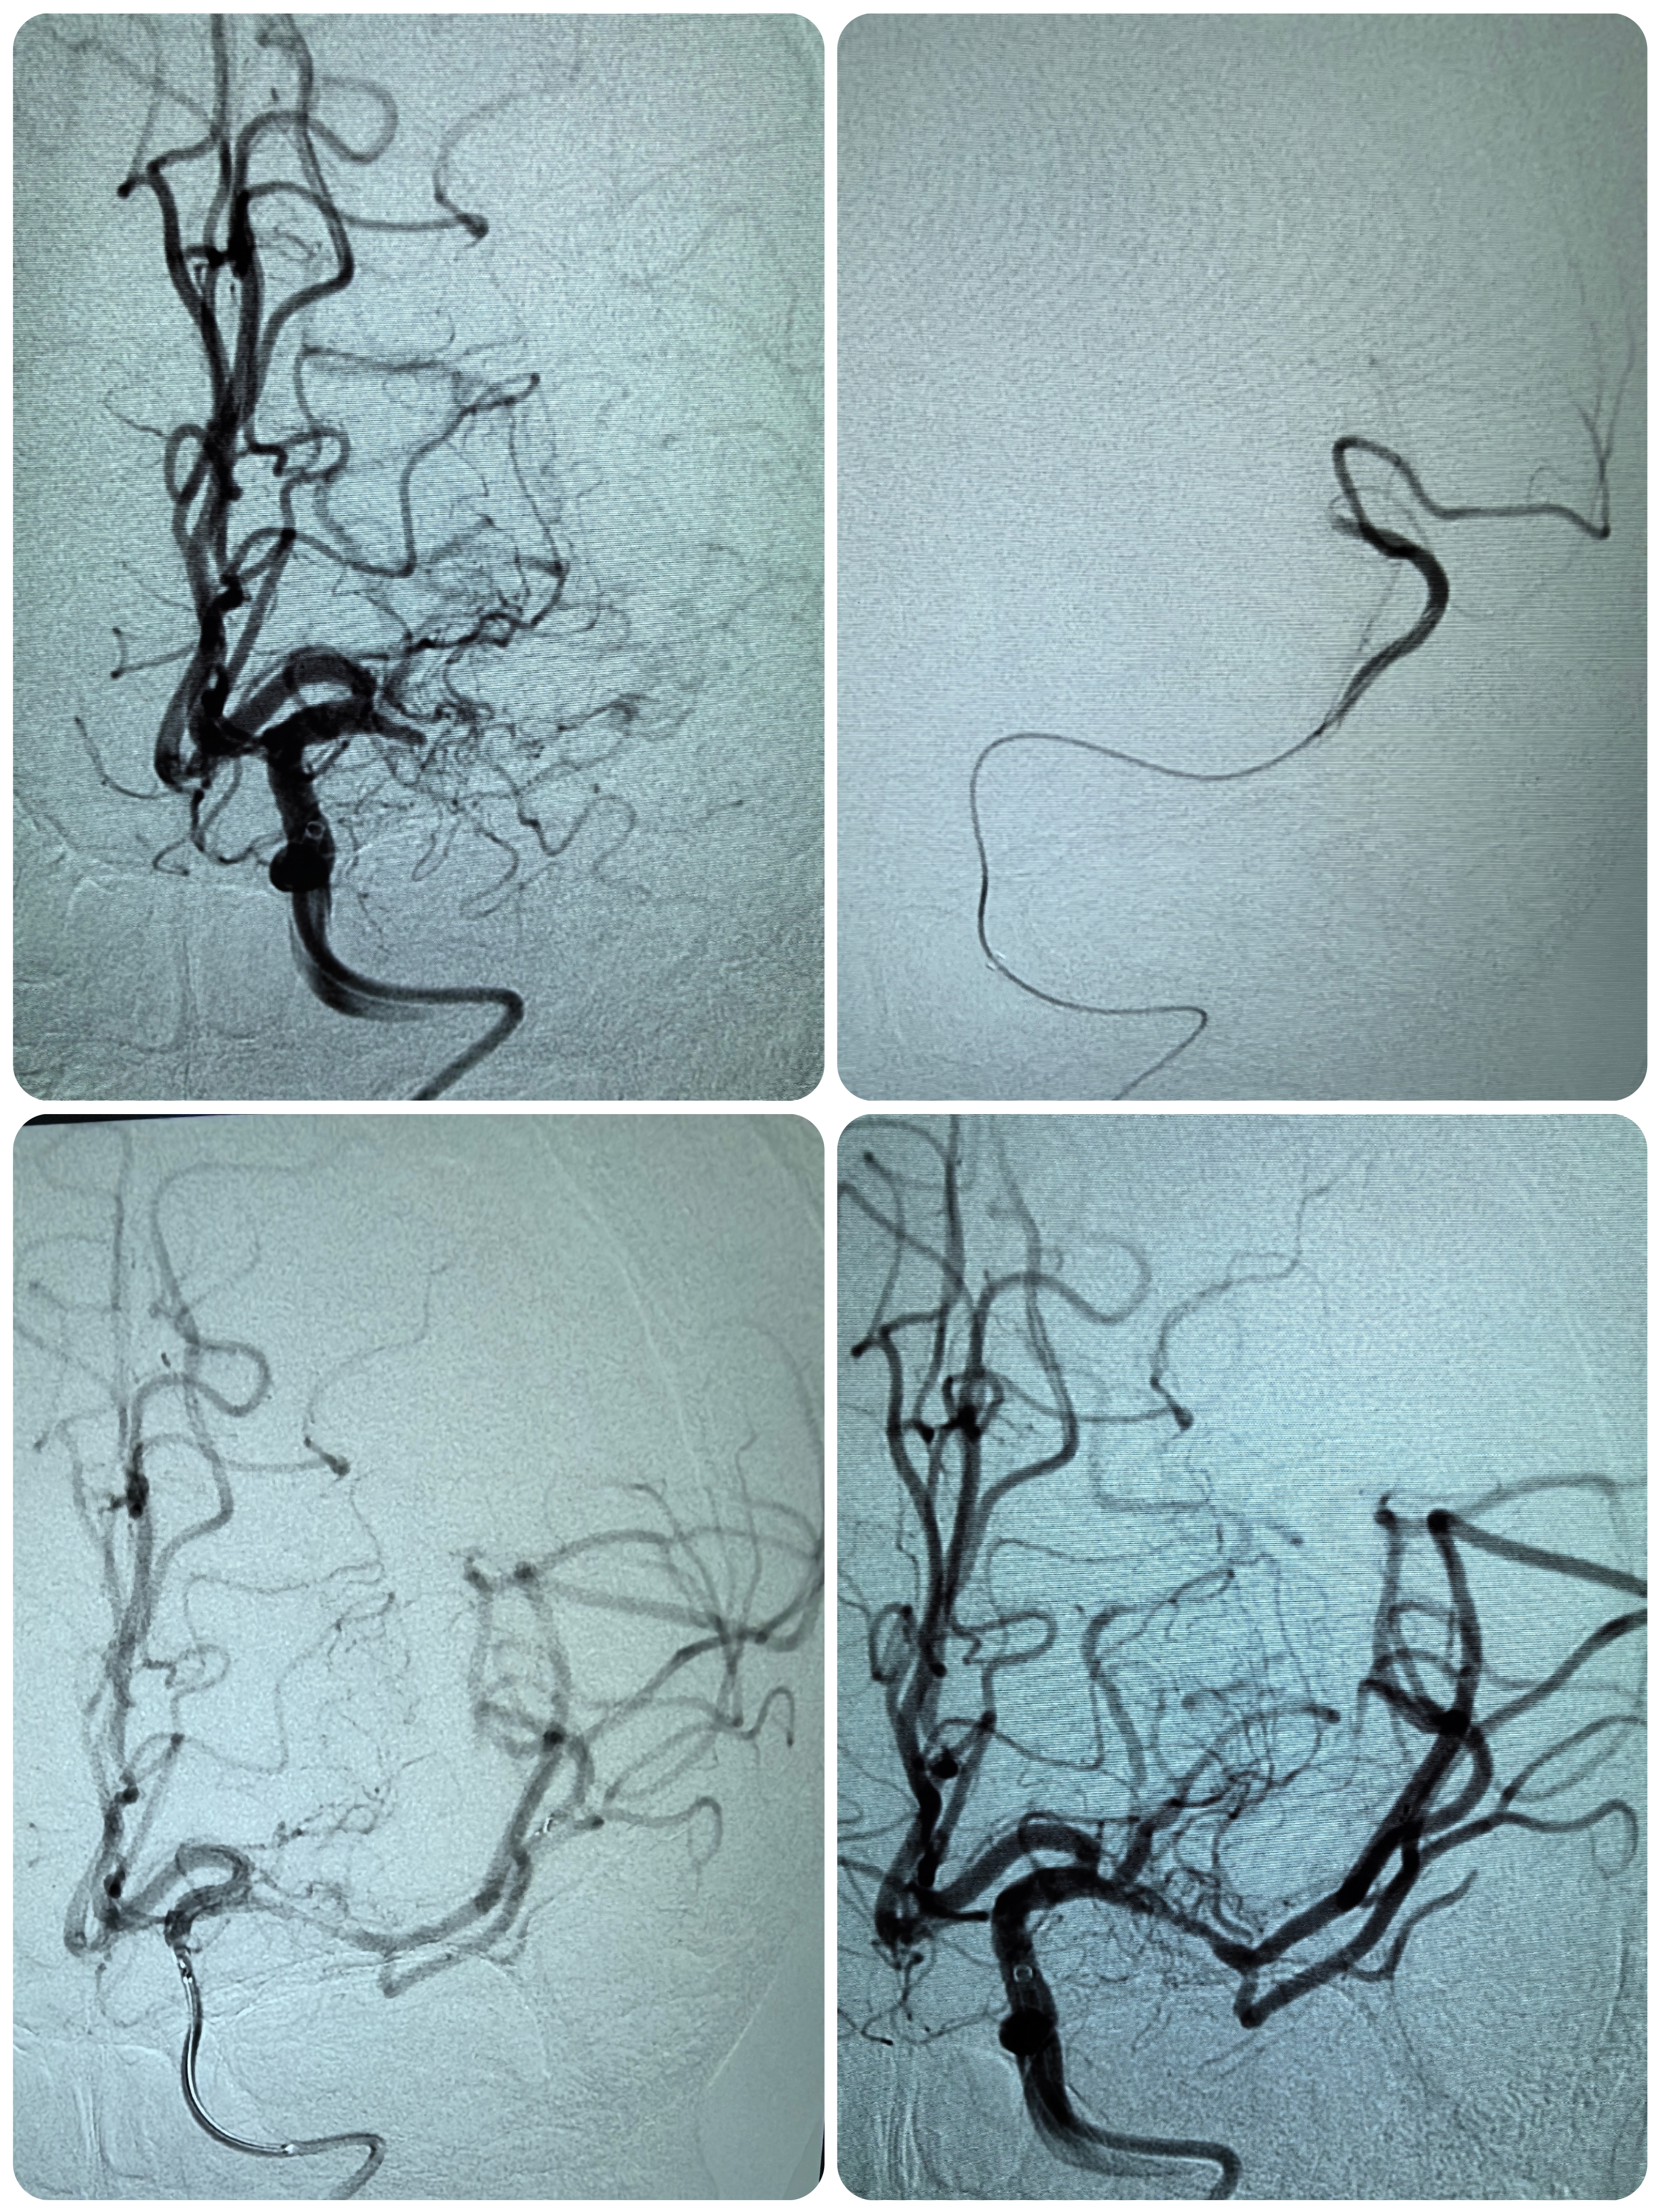

1、本例患者老年女性,系骨科术后次日醒后卒中,经核磁评估提示左侧大脑中动脉闭塞,系责任血管,患者心电图示房颤,考虑心源性栓塞可能性大。

2、本例患者SWIM技术取栓一次后血管再通,颅内血流通畅。